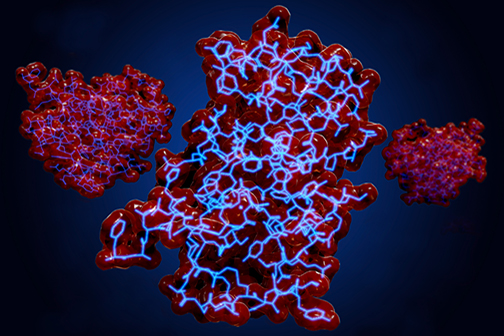

Scientists at LSU Health New Orleans’ Neuroscience Center of Excellence, led by Nicolas Bazan, MD, PhD, Boyd Professor and Director, have identified a new mechanism that regulates a protein key for cell survival. It appears to protect against the excessive oxidative stress that precedes the development of neurodegenerative diseases of the brain and eye. More

LSU Health New Orleans Researchers Discover a Key Failure in AMD that May Lead to Progression & Vision Loss

Research led by Nicolas Bazan, MD, PhD, Boyd Professor, Ernest C. and Yvette C. Villere Chair for the Study of Retinal Degeneration, and Director of the Neuroscience Center of Excellence at LSU Health New Orleans School of Medicine, suggests that age-related macular degeneration (AMD) decreases an essential fatty acid, preventing the formation of a class of protective molecules and reducing repair potential. The discovery may also open new therapeutic avenues for AMD. More

LSU Health New Orleans Researchers Discover Potential New Rx Strategy for Ischemic Stroke

A study conducted by scientists at LSU Health New Orleans’ Neuroscience Center of Excellence reports that the additive neuroprotection of a combination of two omega-3 fatty acid-derived signaling molecules is more effective in protecting brain cells and increasing recovery from stroke in an experimental model than a single drug. More

Study Reports Potential Target and Compounds to Slow the Development of Alzheimer’s Disease

Researchers at LSU Health New Orleans Neuroscience Center of Excellence and Karolinska Institutet have discovered a potential biomarker for Alzheimer’s disease diagnosis that may also serve as a therapeutic target. Examining cerebrospinal fluid samples from patients with cognitive impairment ranging from subjective impairment to a diagnosis of Alzheimer’s disease, they found a shift in the profile of specialized lipid mediators from pro-resolving to pro-inflammatory. The results of the exploratory study are published in the Springer journal, Cellular and Molecular Neurobiology. More

Study Shows That Intranasal Rx Halts Memory Decay in Experimental Alzheimer’s Model

A research collaboration between scientists at LSU Health New Orleans and the Karolinska Institutet in Sweden has found that applying specialized pro-resolving lipid mediators intranasally arrested memory loss and brain degeneration in an experimental model of Alzheimer’s Disease (AD). The results are published in the Nature journal, Communications Biology. More